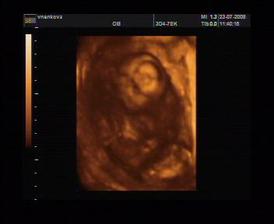

23.7. první 3D ultrazvuk (v 15+3) - jedním slovem úžasný!!! 🙂